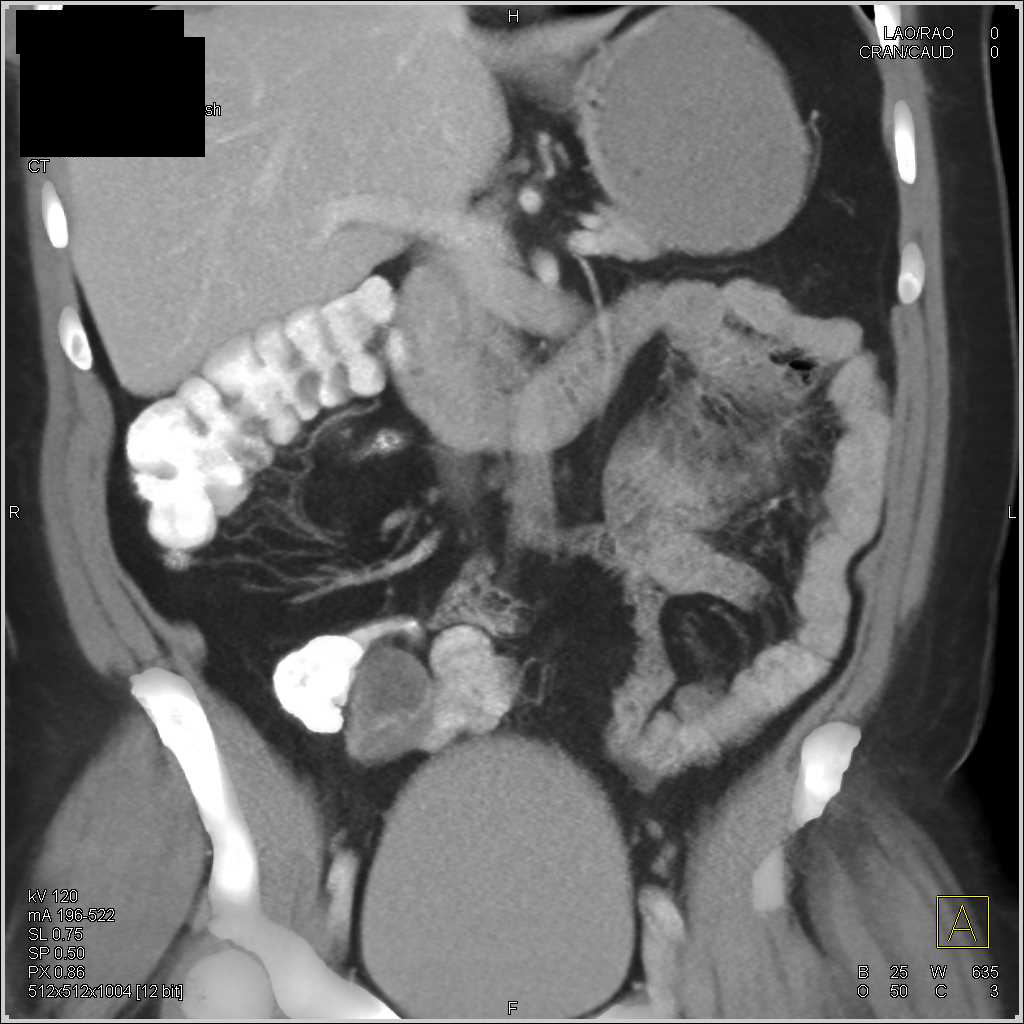

Ulcerating Rectal Cancer